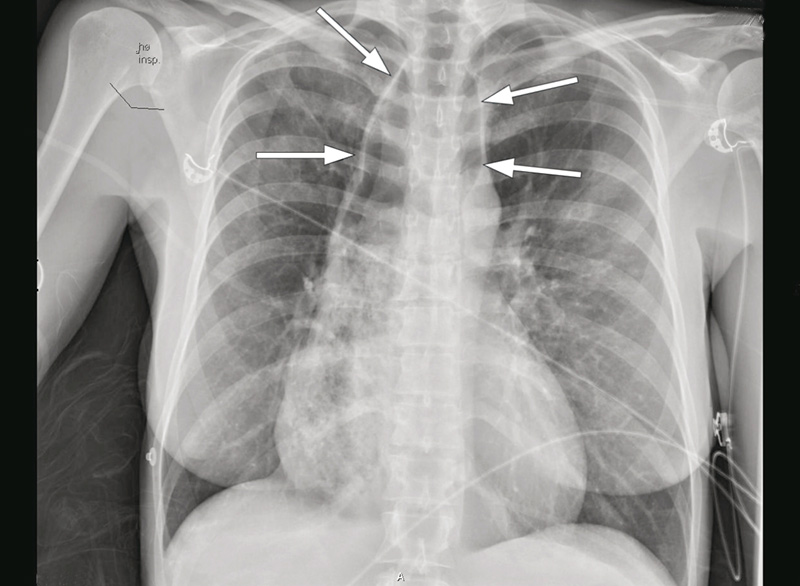

Den respiratoriske acidosen ble normalisert innen 60 minutter. Kvinnen ble etter kort tid ekstubert og var respiratorisk stabil etter dette. Gjentatte røntgen thorax innkomstdagen viste imidlertid vedvarende luft i mediastinum, og tentativ diagnose ble pneumomediastinum (fig 1).

Vi mistenkte nå oesophagusakalasi. Luften som var projisert over mediastinum ved innkomst (fig 1), var sannsynligvis luft i en dilatert oesophaugus og ikke uttrykk for pneumomediastinum, som først antatt. MR oesophagus viste slynget og dilatert (> 6 cm proksimalt) oesophagus med innhold, stenose ved overgangen til ventrikkel og små bilaterale lungefortetninger. Det var bildemessig ikke mistanke om stenoserende malignitet (fig 2).